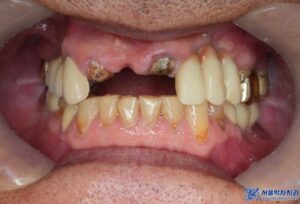

위 환자분은 앞니가 많이 불편해서

임플란트 치료를 고민하고 계셨는데요.

치아를 확인해보니 앞니 두 개는

치아의 뿌리 부분만 남아 있었고,

심한 치주염과 충치로 인해

유지하기 어려운 상태였습니다.

또한, 고혈압과 당뇨 등 만성질환이 있으셔서

치료 진행에 있어 더욱 세심한 접근이 필요했으며,

환자분의 건강 상태를 고려하여 복용 중인

약을 꼼꼼히 확인한 후 치료를

진행하기로 계획하였습니다.